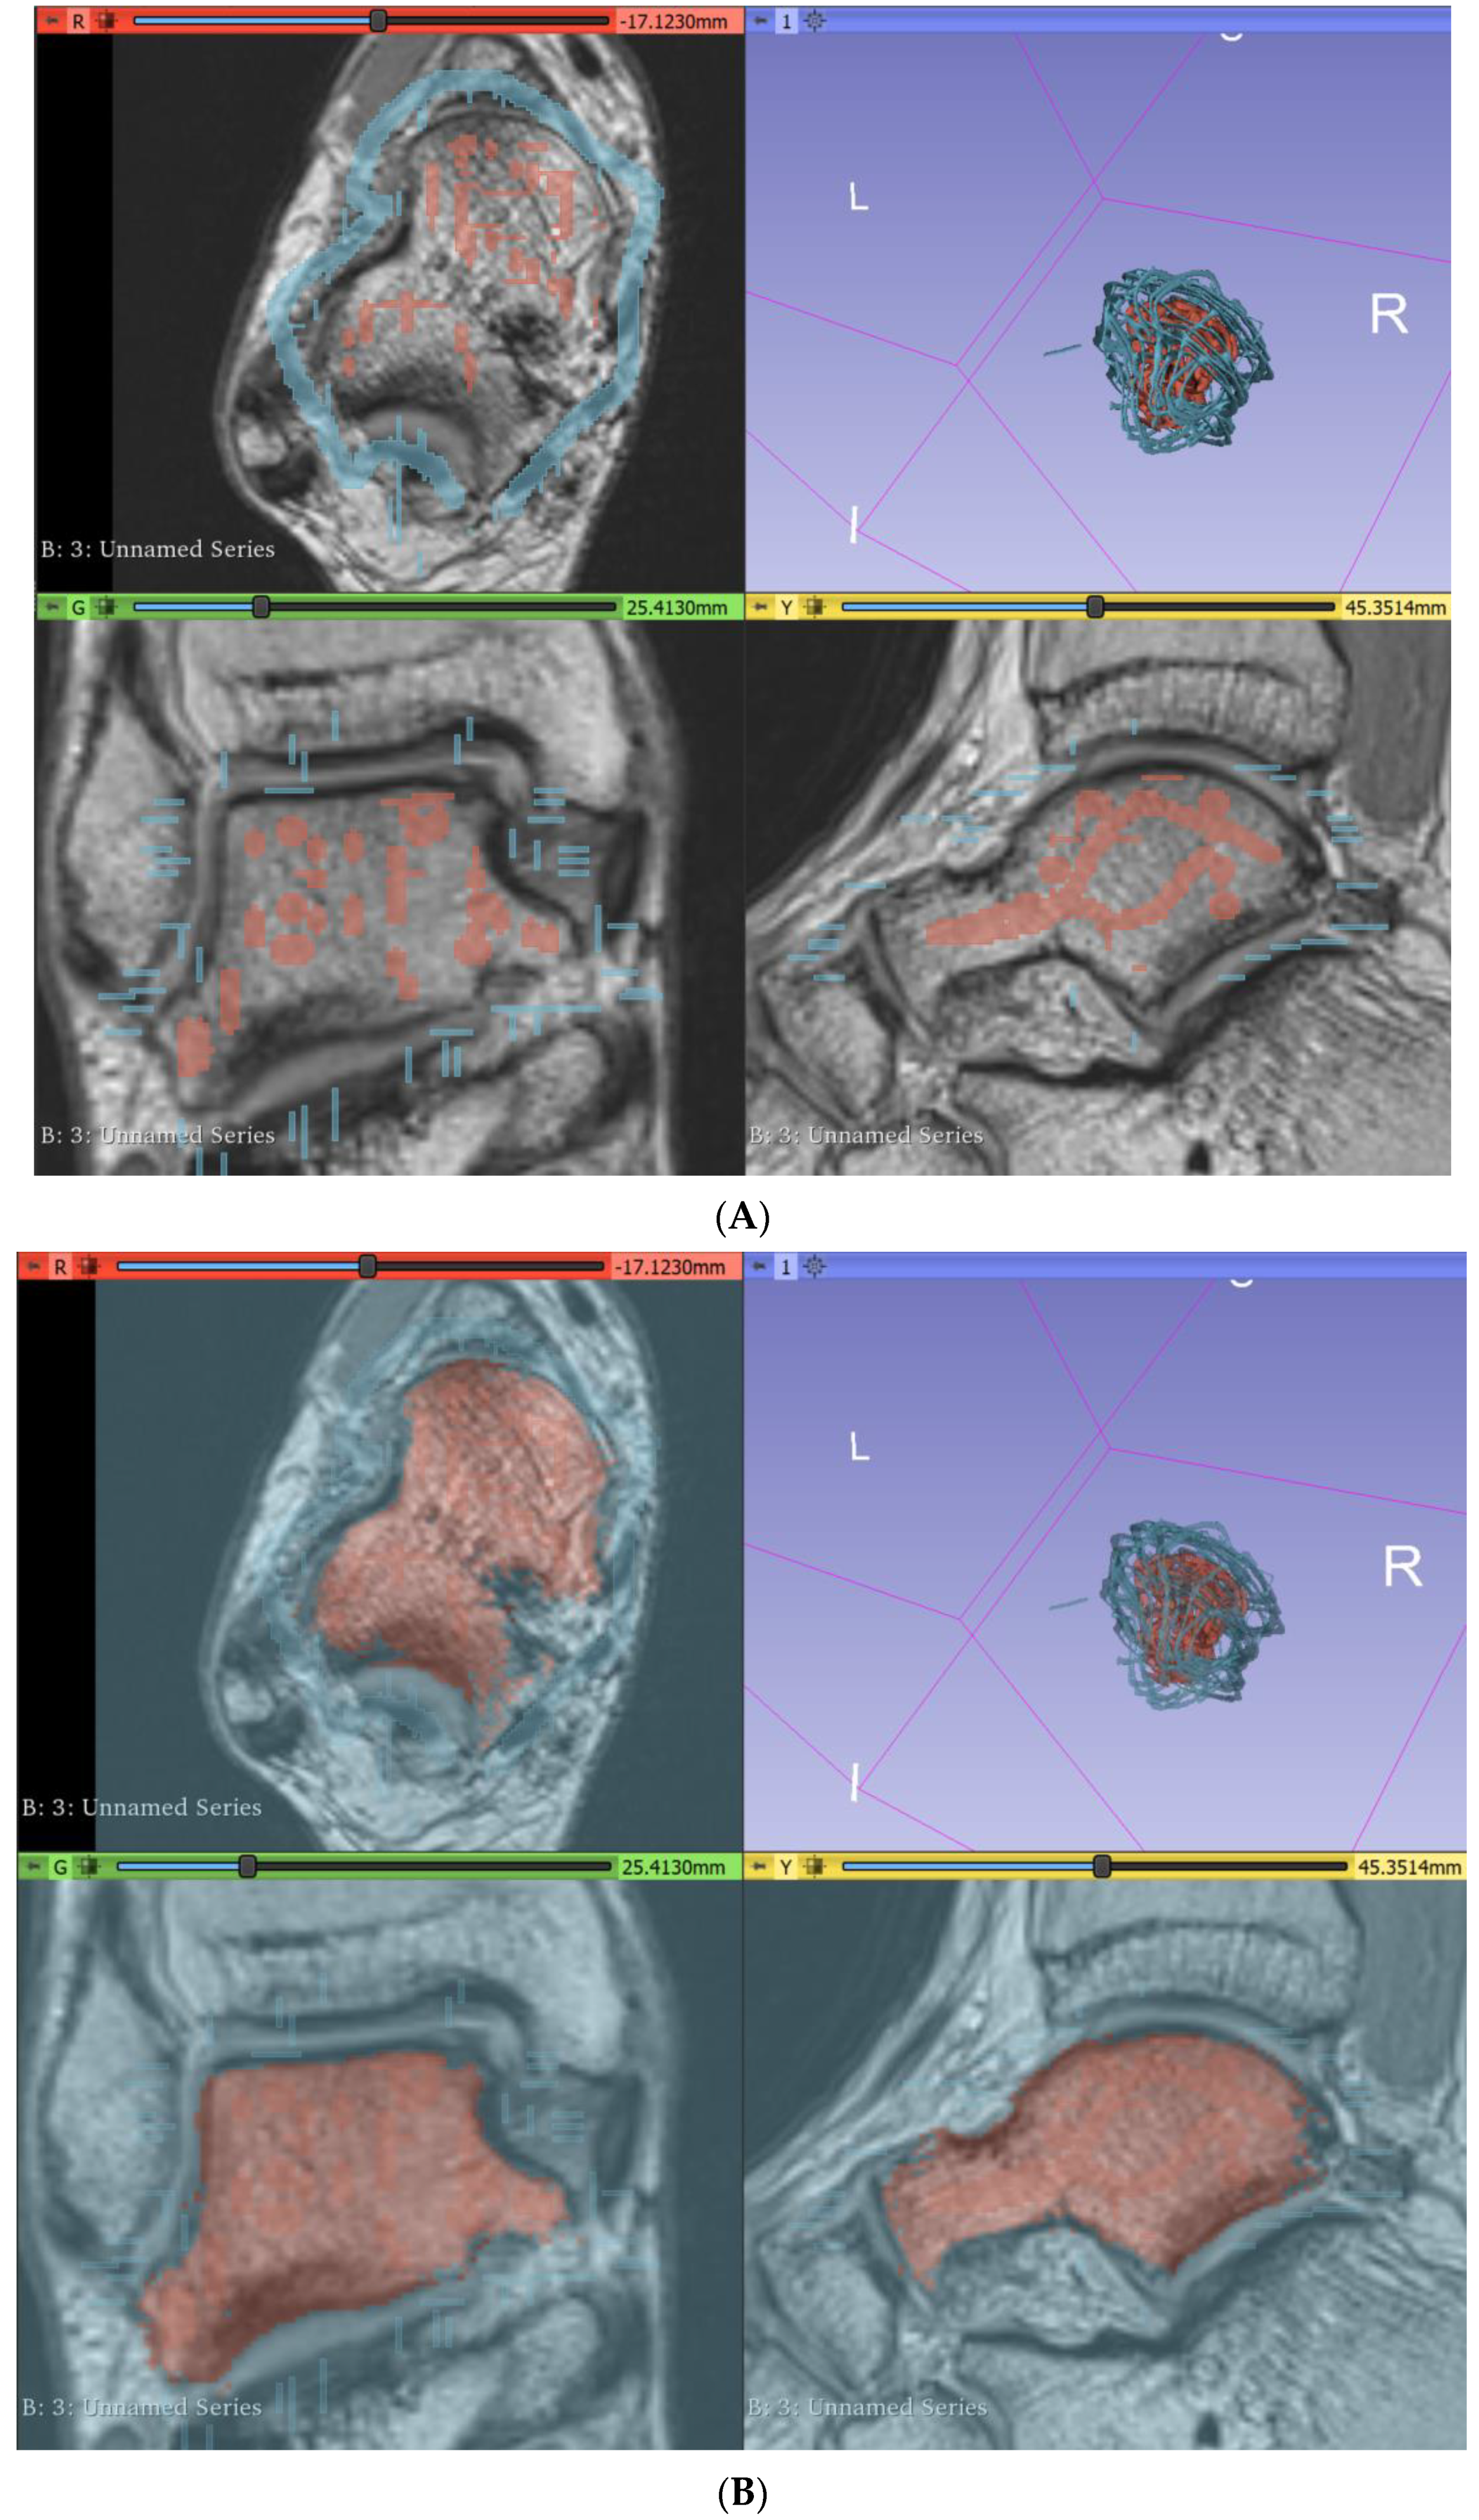

2.1. Image Processing and Segmentation of MRI Dataset Using 3D Slicer

2.3. Segmentation of Musculature